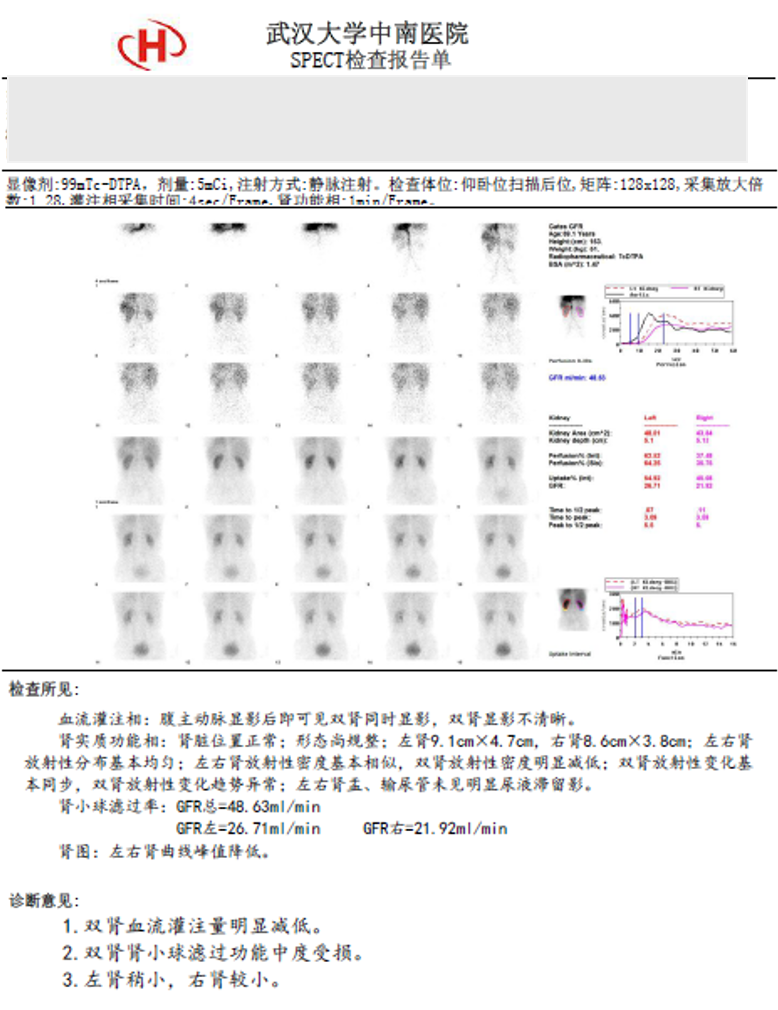

ECT:

换气试验下双侧额顶颞枕叶、右侧基底节及右侧丘脑区脑组织血流灌注量减低,以右侧为著。

左侧小脑组织血流灌注量减低。